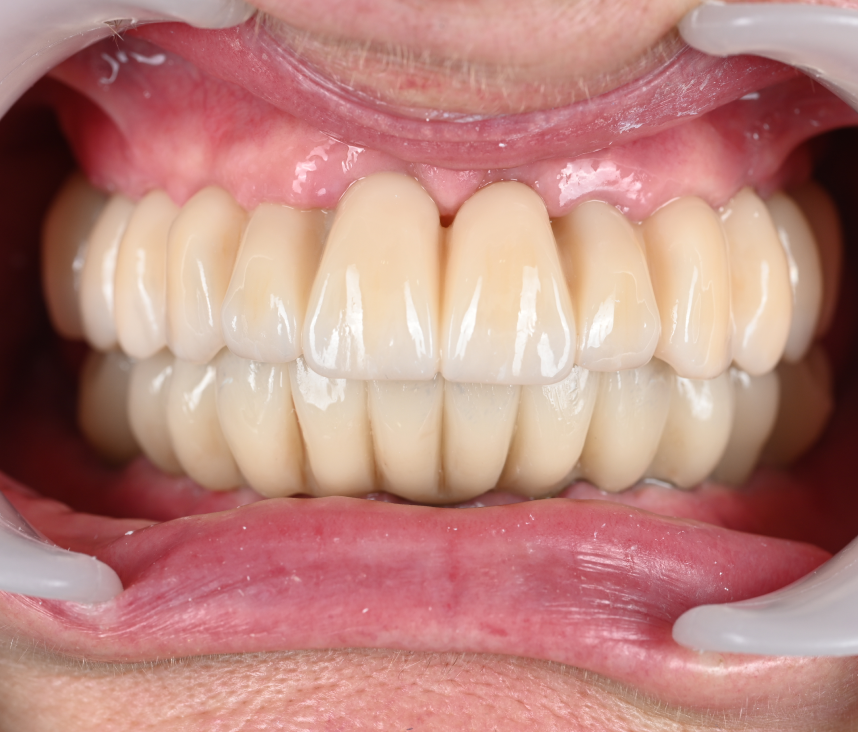

Cas cliniques

La réhabilitation globale est une solution complète pour ceux qui ont des problèmes de santé bucco-dentaire multiples et complexes. Elle consiste en un plan de traitement personnalisé, conçu pour traiter toutes les affections dentaires en une seule fois. Cette approche globale permet de restaurer l’harmonie du sourire, tout en améliorant la santé bucco-dentaire de façon durable.

Au cabinet dentaire du Docteur Malthieu, nous croyons fermement que la réhabilitation globale est souvent la meilleure voie à suivre pour nos patients. Elle offre des avantages indéniables, notamment une efficacité de traitement accrue et des résultats durables. La réhabilitation globale peut traiter simultanément plusieurs problèmes, ce qui minimise le nombre de visites nécessaires et réduit les délais de guérison.